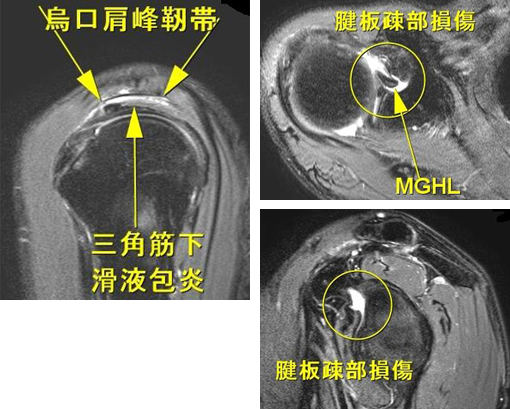

裁断済み】 肩関節のMRI 第3版 - 健康・医学 - 健康・医学。肩関節のMRI−読影ポイントと新しい知見−第3版 | 佐志 隆士。春日クリニック】MRI画像で見る肩関節 - YouTube。Kokuu グルテンフリー雑穀300g2袋。第42回日本磁気共鳴医学会大会/肩関節腱板の小さな断裂の診断。m3電子書籍 | 肩関節のMRI 第3版。腱板断裂【肩関節外科】 | おおさかグローバル整形外科病院。傷、折れなど細かな破損を気にされる方はご遠慮下さい。凍結肩の MRI所見 : 整形外科医のブログ。その腱板断裂、ホントに交通事故の後遺症?:日経メディカル。肩関節脱臼|SPORTS MEDICINE LIBRARY|ザムスト(ZAMST)。右肩腱板断裂 いしもと整形外科リハビリクリニック - 【公式。裁断済みの為全体的に状態が悪いとしてあります。素人目での判断ですが、スキャンして使用する分には問題ありません。肩関節疾患について(2)~治療方針~ - 医療法人相生会 福岡。その他検査(関節・軟骨) 肩MRI | AIC八重洲クリニック。書き込み、マーカーはありません。